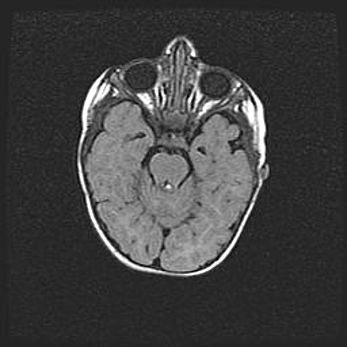

Множественные кисты обоих полушарий головного мозга, наибольшая из них в правой затылочной области. Ассиметричная атрофическая гидроцефалия.

Возраст: 7 месяцев

Вес: 5660 г

Пол: мужской

Окружность головы: 41,5 см

Срок гестации: 28-29 недель

Кисты головного мозга развиваются в результате многоочаговых некрозов вещества мозга и возникают вследствие перенесенной перинатальной инфекции, менингитов, энцефалитов, асфиксии, родовой травмы, расстройств мозгового кровообращения различного генеза. Образованию кист в веществе головного мозга плодов и новорожденных способствуют такие факторы, как высокое содержание в нем воды, недостаточная (или отсутствие) миелинизация и слабая астроглиальная реакция на повреждение.

Кисты могут сочетаться с гидроцефалией и другими поражениями головного мозга.